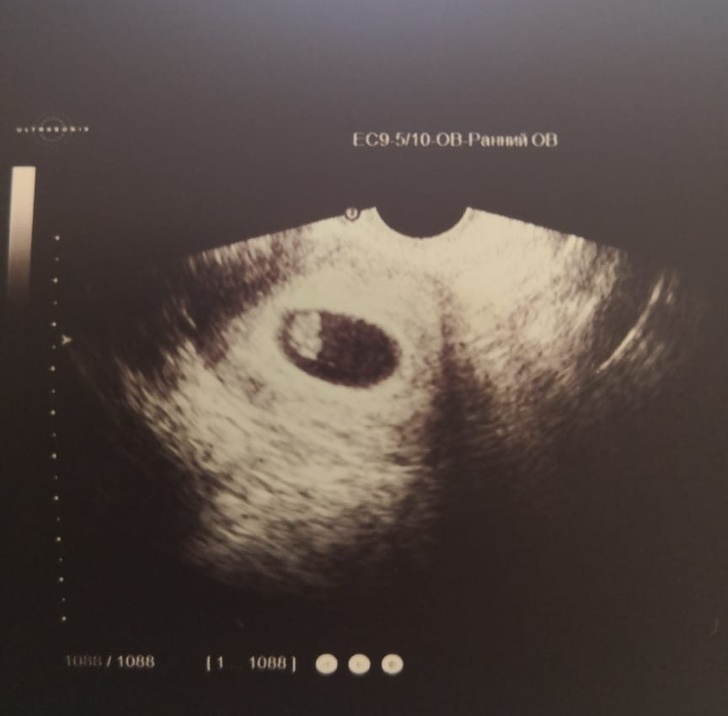

«Дізнався, що стану батьком»